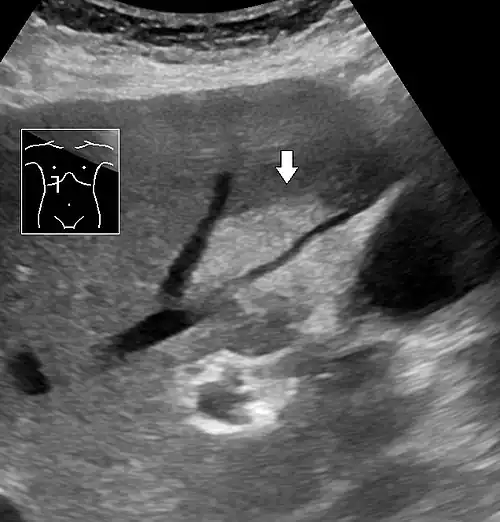

On X-ray computed tomography (CT), the increased fat component will decrease the density of the liver tissue, making the image less bright. Typically the density of the spleen and liver are roughly equivalent. In steatosis, there is a difference between the density and brightness of the two organs, with the liver appearing darker.[12] On ultrasound, fat is more echogenic (capable of reflecting sound waves). The combination of liver steatosis being dark on CT and bright on ultrasound is sometimes known as the flip flop sign.

On abdominal ultrasonography, steatosis is seen as a hyperechoic liver as compared to the normal kidney.

Abdominal ultrasonography of focal steatosis. It is distinguished from a tumor by not compressing the hepatic vein.